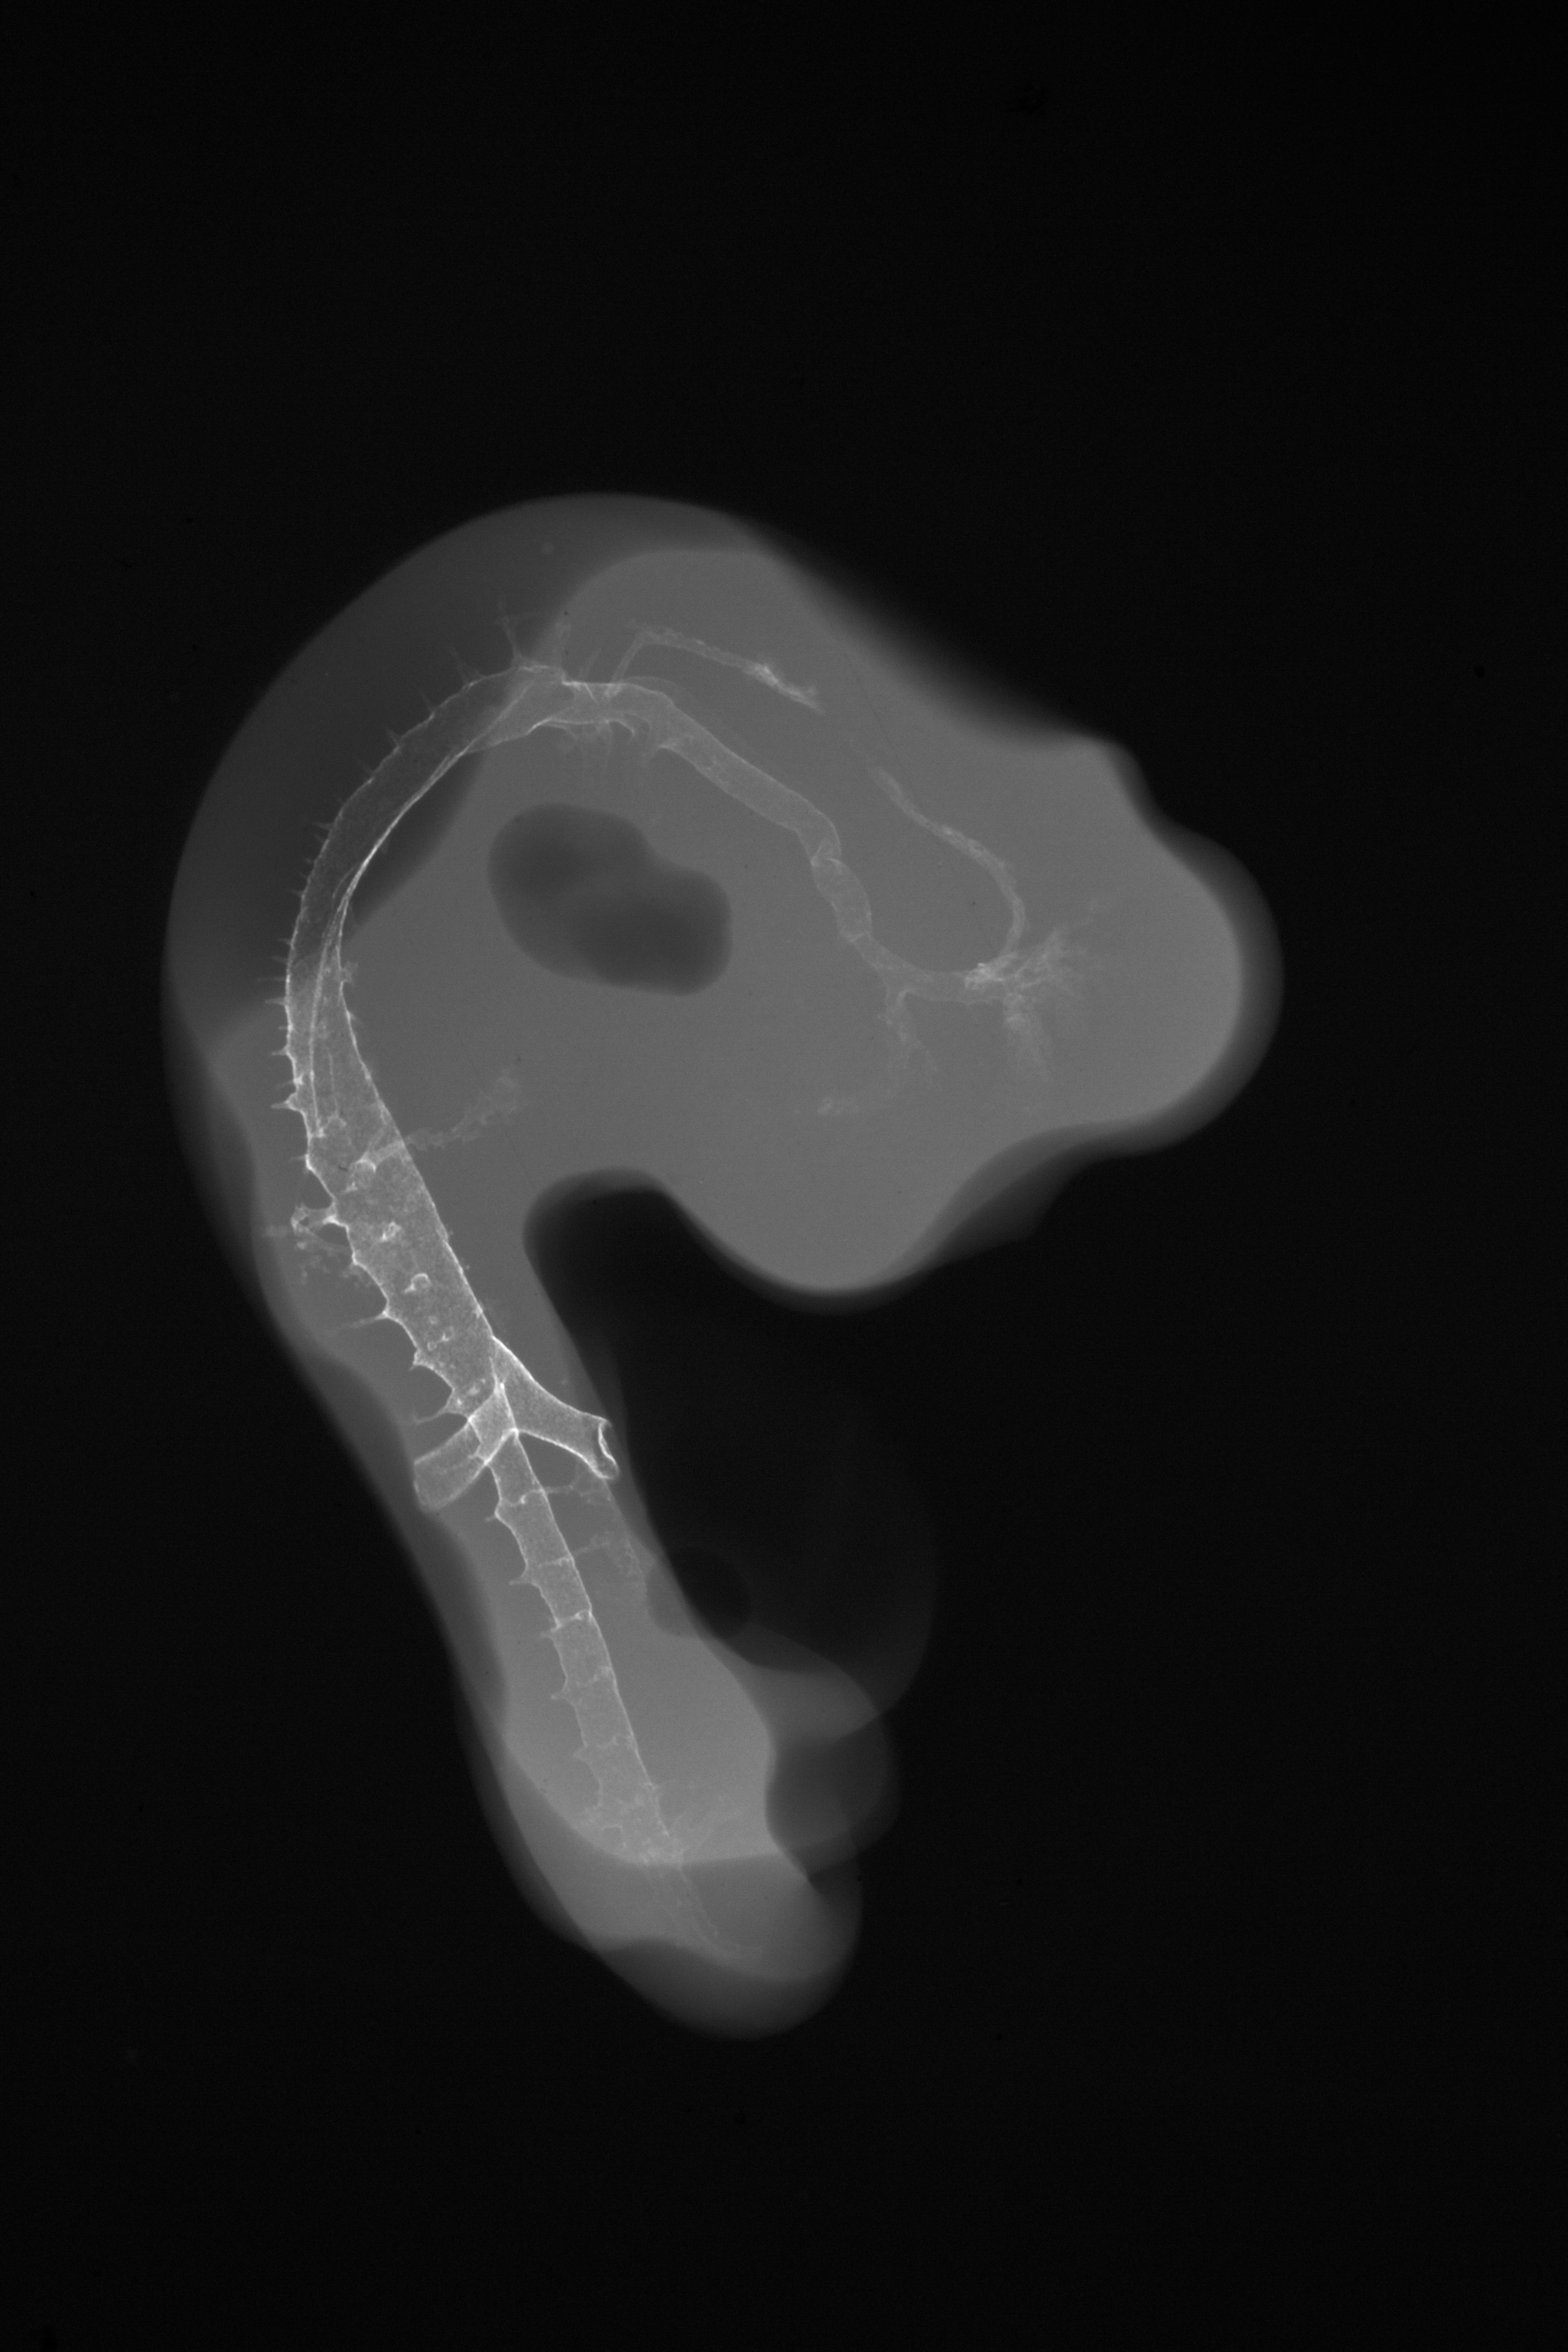

Chick Embryo Microangiography

Hamburger-Hamilton (HH) Stage 23 (approx. 4 days)

X-Ray Micrographs